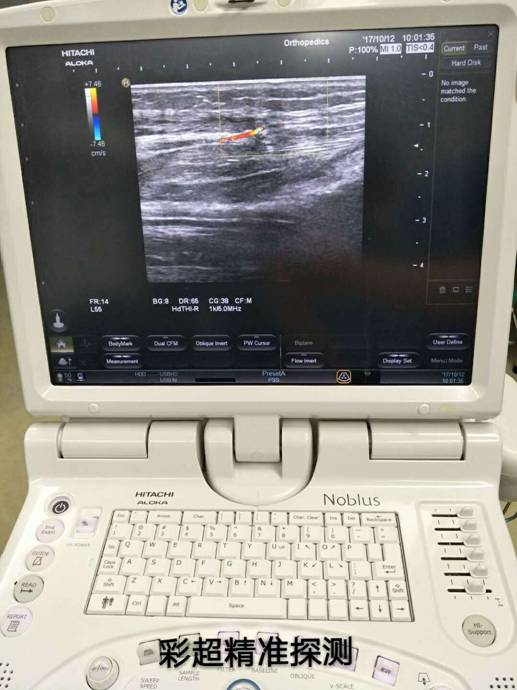

衡陽市中心醫(yī)院彩超定位精準治療骨折修復皮瓣

近一個月來,衡陽市中心醫(yī)院收治了多位外傷導致小腿多處粉碎性骨折,小腿部分皮膚軟組織缺損、骨(肌腱)外露的患者,醫(yī)院燒傷整形科、骨科、超聲科多科協(xié)作,通過施行彩超定位下,小腿穿支皮瓣轉移修復創(chuàng)面手術,均取得良好的手術效果,極大地減輕了患者的疼痛和創(chuàng)傷。

骨科根據(jù)患者骨折情況分別施行骨折復位+內(nèi)(外)固定術,然后由燒傷整形科根據(jù)患者皮膚軟組織缺損情況,制定小腿穿支皮瓣轉移修復創(chuàng)面方案。為保證手術成功率,燒傷整形科會同超聲科由黃道遠主任于術前利用彩超精準的探測小腿術區(qū)的各個動脈穿刺,并逐一標記,再由燒傷整形科手術團隊根據(jù)動脈穿支的分布情況設計皮瓣,施行小腿穿支皮瓣轉移修復術。

由于采用了彩超定位技術,使得皮瓣設計方案更合理,手術操作更精準,手術耗時更少,更因為保護好了血管,術后皮瓣腫脹,存活均較以往有明顯改善,手術效果得到極大保障,患者滿意度大大提高。